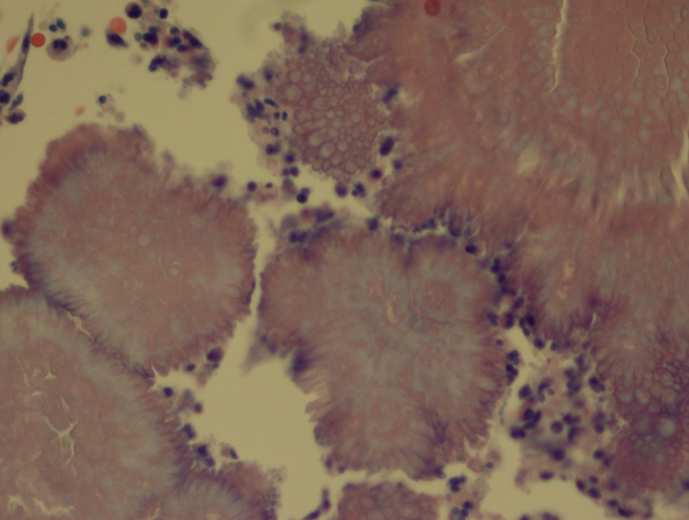

Pelvic exam revealed a benign appearing cervix that was not painful to touch or motion. There was a clear to white mild discharge that was suspected to be normal vaginal secretions. IUD strings were noted. Colposcopy revealed an easily appreciated transformational zone without any obvious lesions. A routine endocervical curettage (ECC) was performed followed by observed increased clear discharge from the cervical os. ECC was sent for routine pathology: